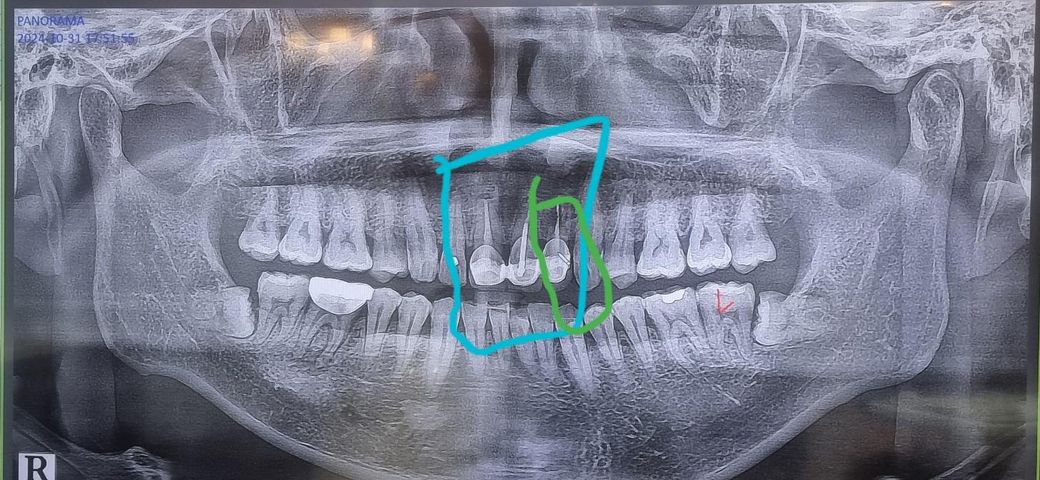

앞니 브릿지 교체할려고 합니다(임플란트x)

예전에 사고로 윗니 3개를 신경치료하고

브릿지를 걸었습니다

최근 잇몸이랑 브릿지가 벌어져

음식물이 끼는게 심해져서 다시 할려고 합니다

14년전에 했던 보철입니다

치과 3군데를 갔는데 초록색으로 된곳은

뜯어봐야 아는데 뼈가 녹고있다고

발치를 해야 된다고들 다들 하네요

그 자리는 뼈가 너무 얇아서 뼈이식이나 임플란트는 안된다고 합니다 치과3개 동일 한다해도 8개월은 걸리고 39살인데 심미성이 안 좋을꺼다 애기하네요

녹는치아는 빼고 그옆에 송곳니까지 브릿지로 걸자고 하는데 저 상태에서 임플란트없이 치아뽑고 3개만 브릿지 할수는 없나요? 아니면 더 좋은 시술방법이 있을지 문의드립니다